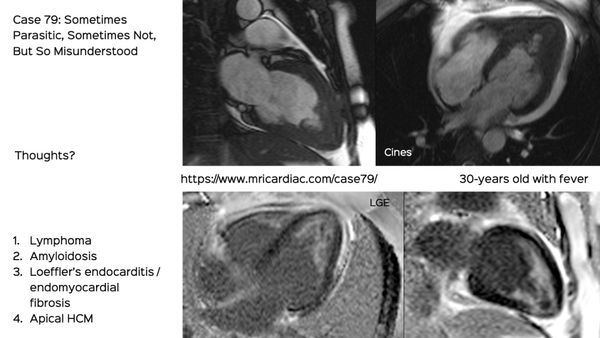

A subendocardial membrane is a distinctive sign of this condition